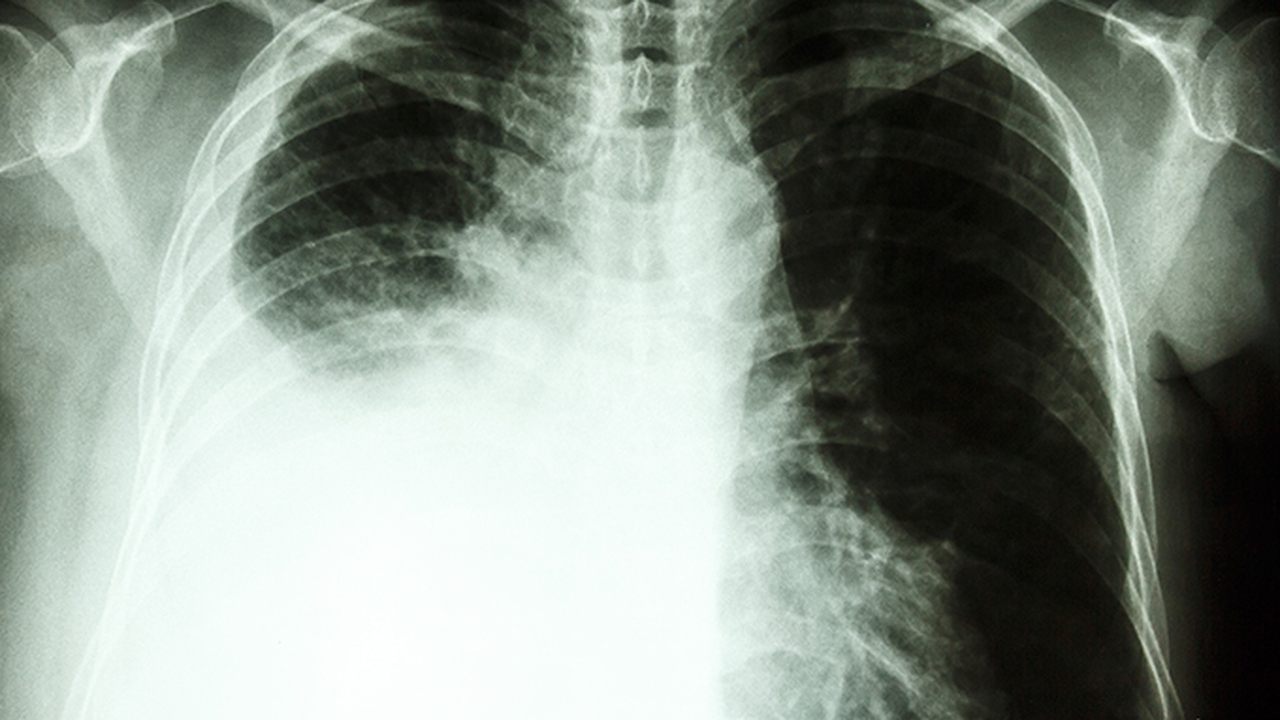

肺气肿是一种慢性阻塞性肺疾病,主要由于长期吸烟、空气污染或遗传因素导致肺泡壁破坏,气体交换功能受损。早期诊断和规范治疗对延缓病情进展至关重要。